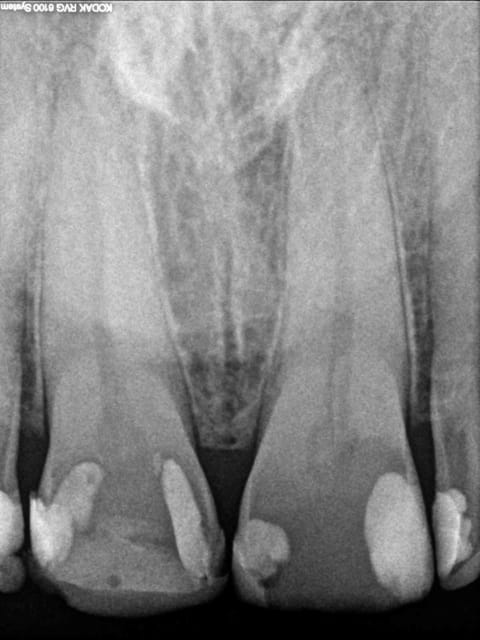

pour comparaisons , voici deux images; l'une capteur kodak 6100 l'Autre julie Krystal X

11 21 afetr5 - Eugenol

029 athojb - Eugenol

> pour comparaisons , voici deux images; l'une capteur kodak 6100 l'Autre julie

> Krystal X

L'image du 6100 est traitée à mort...

Pour comparaison, voici l'image du Krystal X traitée à la truelle, tu conviendras que le résultat approche pas mal de celle du 6100. Avec des données brutes du capteur du Krystal X et des conditions de prise de vue identiques pour les deux images, le résultat serait très approchant, amha.

he ben non !

l'image du 6100 est brute de fonderie comme celle du krystal x.

regarde un peu plus prés les détails et les niveaux de gris sur le 6100.

il y a une nette différence pour moi; au moins celle de ne pas devoir corriger mes images avec photoshop...

> he ben non !

>

> l'image du 6100 est brute de fonderie comme celle du krystal x.

Elle est traitée par le logiciel !

Et pour moi, elle est surtraitée... Ca fait apparaître un halo radioclair autour de chaque obturation qui n'est qu'un artefact de la sharpenisation.